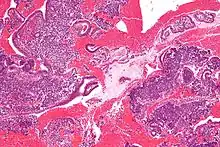

High magnification micrograph of decidualized endometrium due to exogenous progesterone (oral contraceptive pill). H&E stain

Low magnification micrograph of decidualized endometrium. H&E stain

If there is inadequate stimulation of the lining, due to lack of hormones, the endometrium remains thin and inactive. In humans, this will result in amenorrhea, or the absence of a menstrual period. After menopause, the lining is often described as being atrophic. In contrast, endometrium that is chronically exposed to estrogens, but not to progesterone, may become hyperplastic. Long-term use of oral contraceptives with highly potent progestins can also induce endometrial atrophy.[13][14]